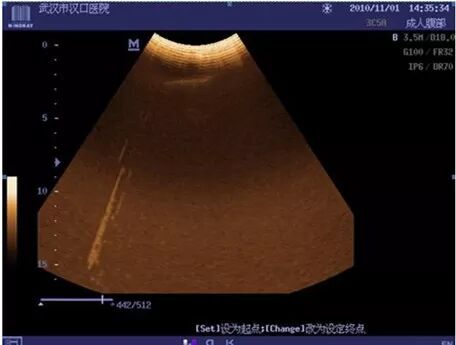

1、超声设备电源线与插座接触不良引起的干扰(DC-6)

现象:干扰束会随机出现在图像的不同区域

原因:电源线与电源插座接触不良,电极易产生电离火花引入电磁干扰,造成图像干扰现象。

处理措施:更换插座孔或新插排。